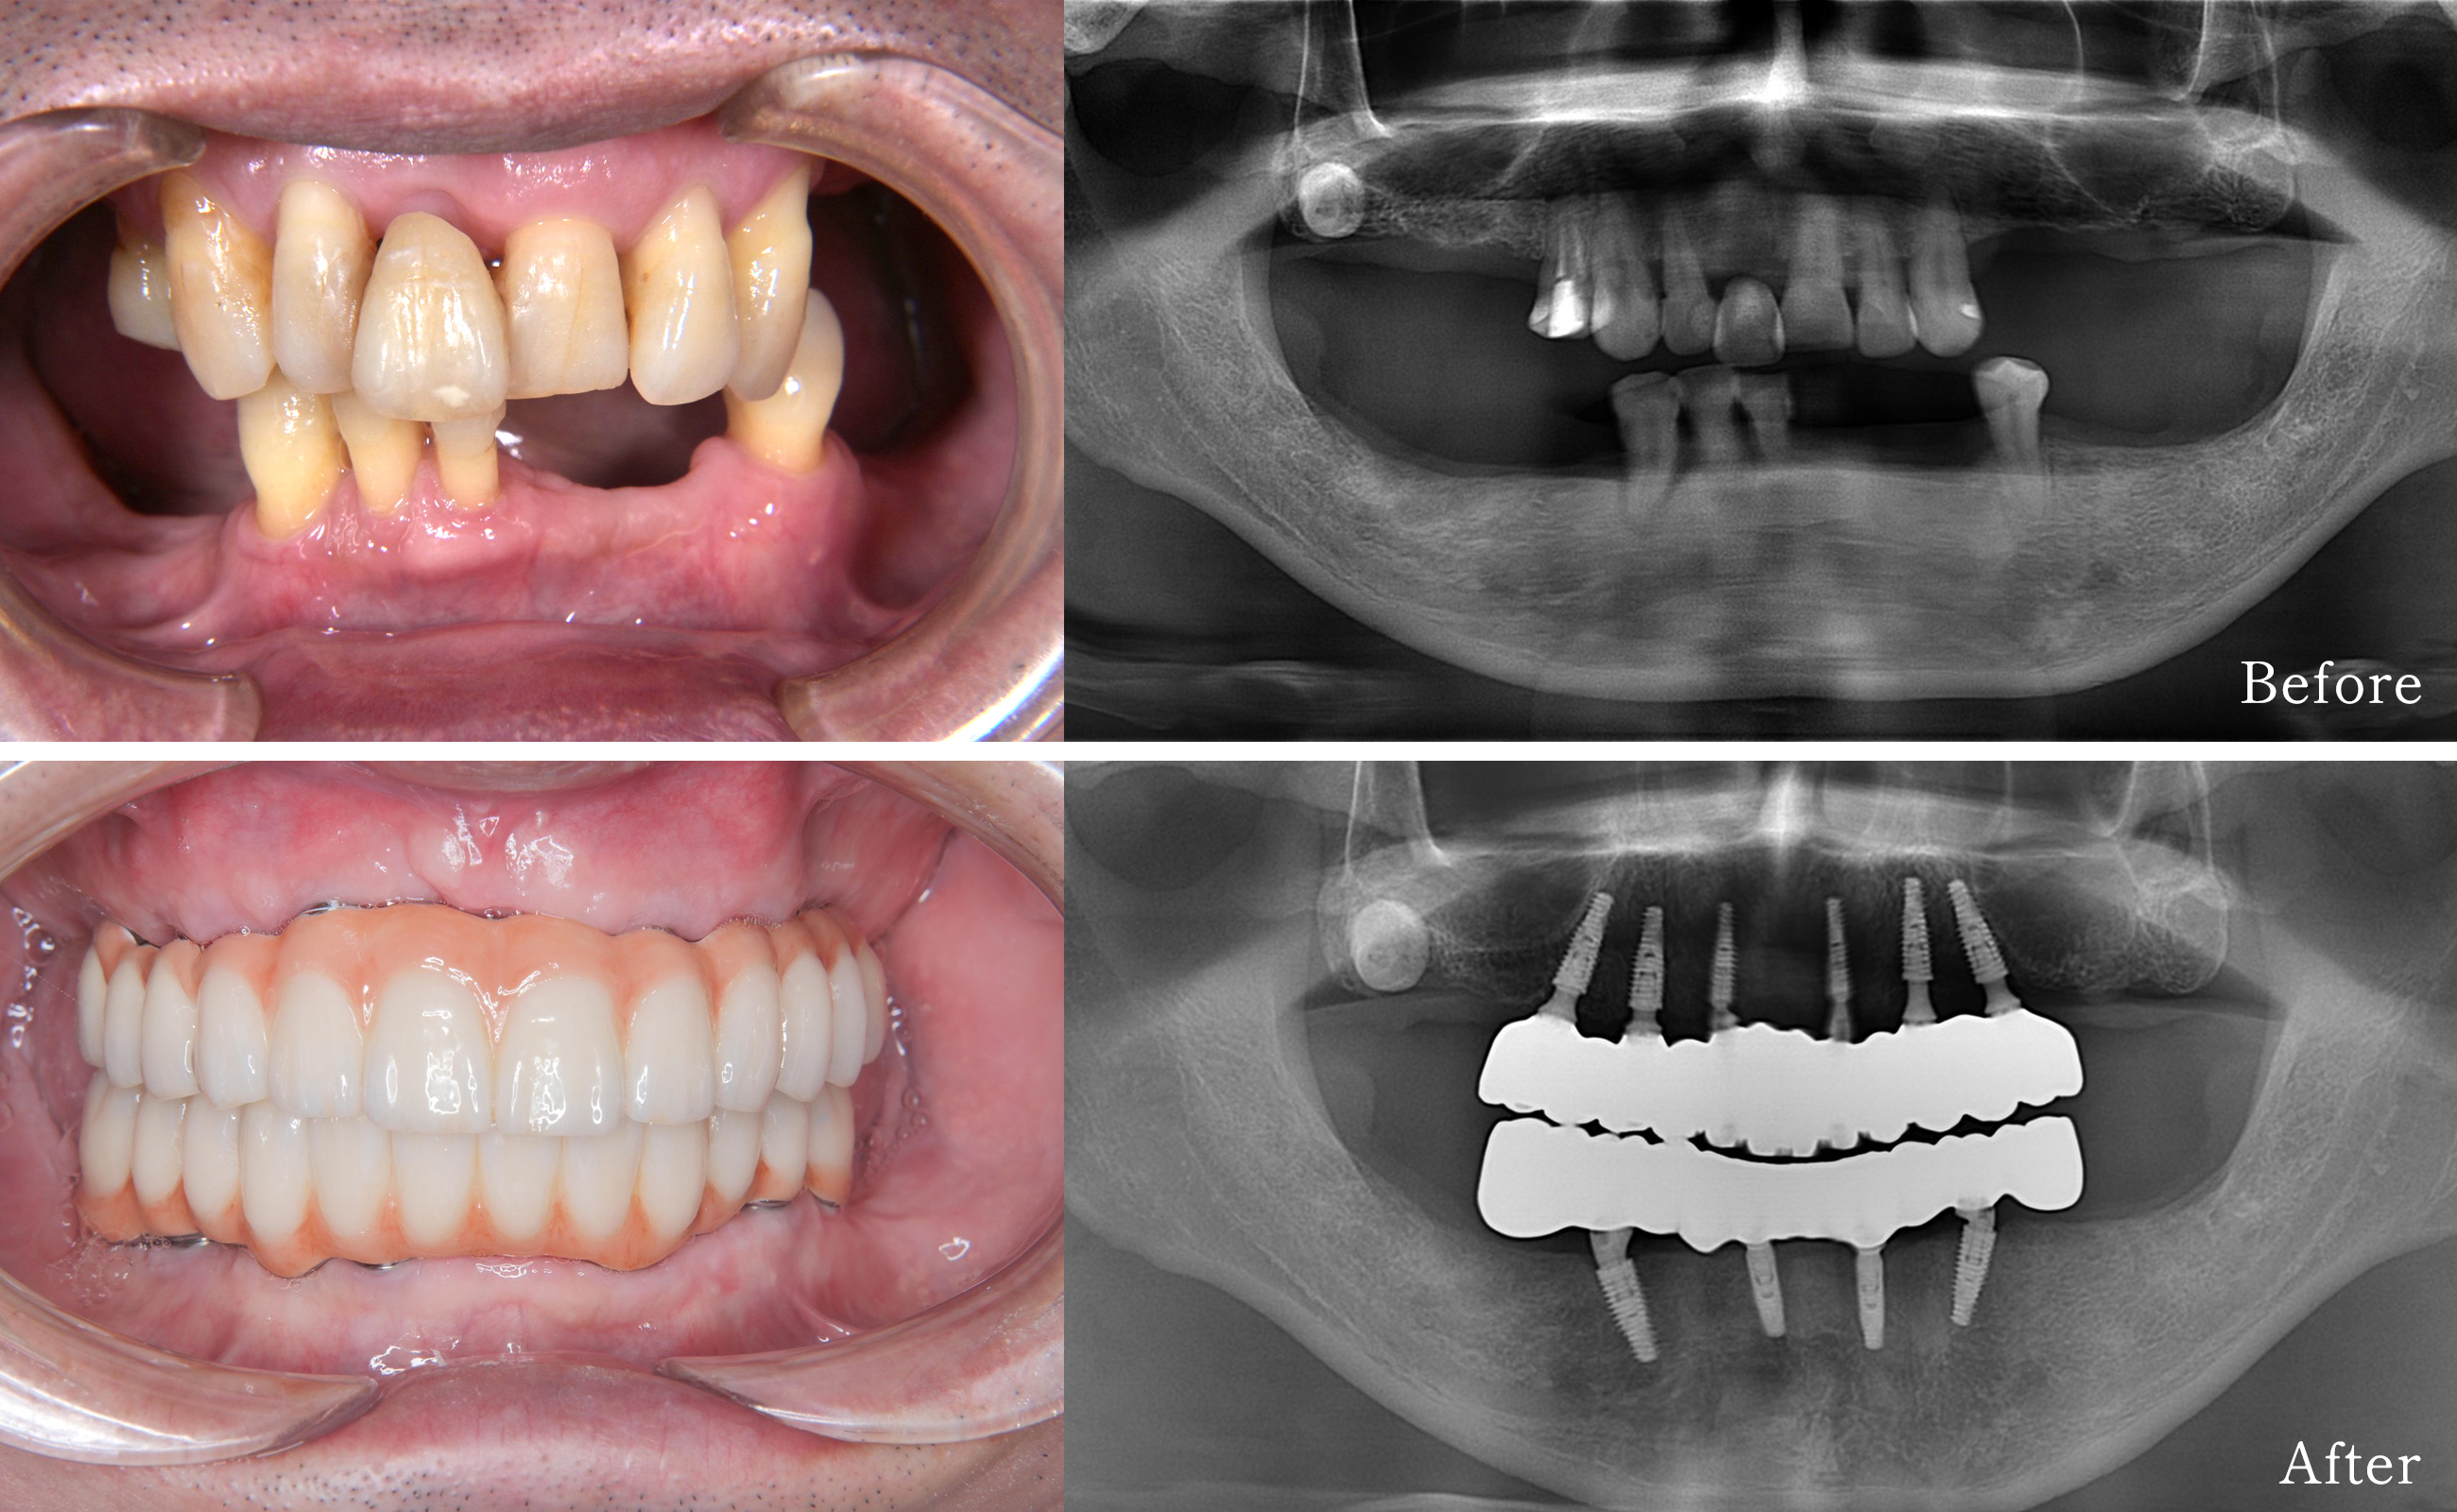

60代・男性/匿名

上顎ALL‑ON‑6+下顎ALL‑ON‑4(ガイデッドサージェリーを併用)による咬合回復の症例紹介

今回は、上下顎のかみ合わせや食事でお困りだった60代の男性の症例についてご紹介します。上顎はALL‑ON‑6(6本のインプラントで上顎の補綴を支持する方法)、下顎はALL‑ON‑4(4本のインプラントで下顎の補綴を支持する方法)を組み合わせて治療を行いました。患者さまの書面による同意を得たうえで、診査・治療の流れや経過、考慮した点をわかりやすく解説します(写真掲載は同意取得済みです)。

初診で口腔内写真、パノラマレントゲン、歯科用CT(CBCT)を撮影し、骨量・骨質、残存歯の状態、上顎洞や下顎管の位置を評価しました。診査の結果、上顎は広範囲の欠損があり安定した支持が求められるためALL‑ON‑6を検討、下顎は前方部の骨量が比較的良好であったためALL‑ON‑4が選択肢に適すると判断しました。治療方針は複数の選択肢を提示し、利点・リスク・費用・期間について十分に説明したうえで、患者さまと相談して決定しました。